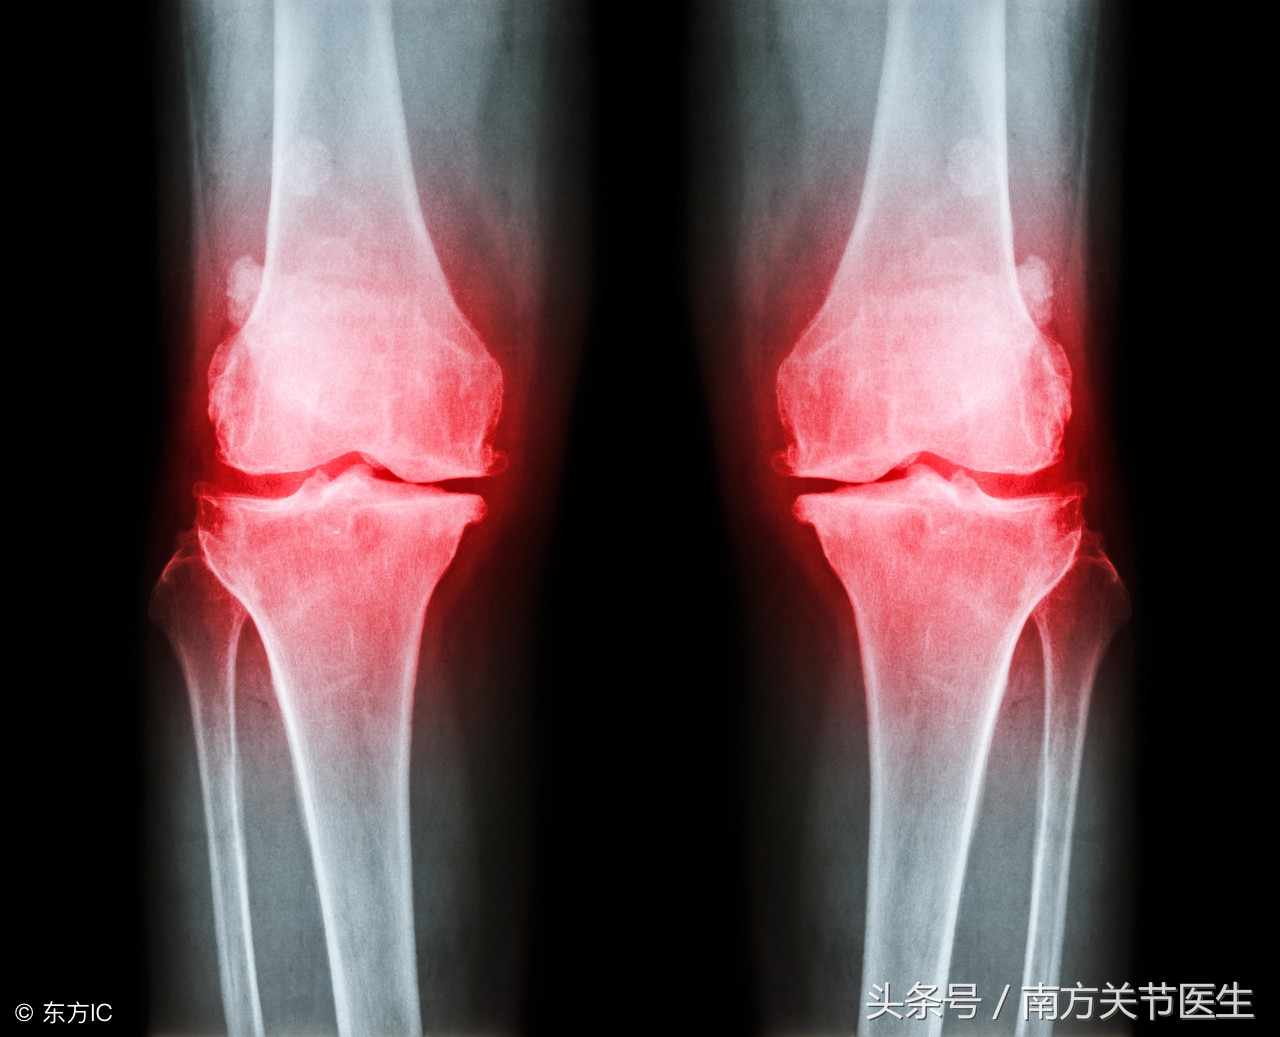

骨质增生治疗方法的选择由症状决定。疼痛是骨质增生的主要症状。若病情严重,会出现关节活动受限或者僵硬、行走困难、跛行等症状。骨质增生大多发生在颈椎和腰椎,膝关节和髋关节发生的可能性相对于前两者来说较小。大多数患者是进行药物治疗的,只有少数特殊的患者需要进行手术治疗。药物治疗的目的主要是缓解症状、解除水肿和炎症反应。通过使用药物来使得受压的神经、血管水肿的滑膜恢复,但是并不一定都能达到目的。

4、膝、髋关节发生骨质增生。患者的骨关节炎明显,而且关节不稳定。或者患者因其关节间隙过多狭窄而感到疼痛,行走受到影响。